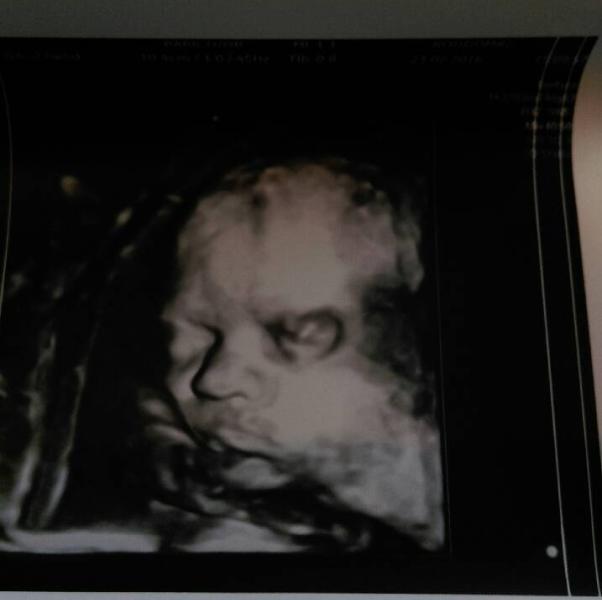

вот такие мы серьезные)) сделали подарок папуле на 23))) весим 1130,большухи совсем,сидим себе на попе и все тут,что мы дурочки вниз головой лежать)) хотя еще может перевернуться,плацента тф тф поднялась) была во 2 рд на 3д узи у Гайдаленок,впечатления супер!! Р.S аж слезку счастья проронила в конце)

номер 2130814,звоните и записывайтесь,мы делали полное узи в 3д формате,плюс гдето 10 фото и видио на флешку,и просто одно распечатанное фото,папу позвали все показали,за все 530 тыс,хотя сразу говорили 580)